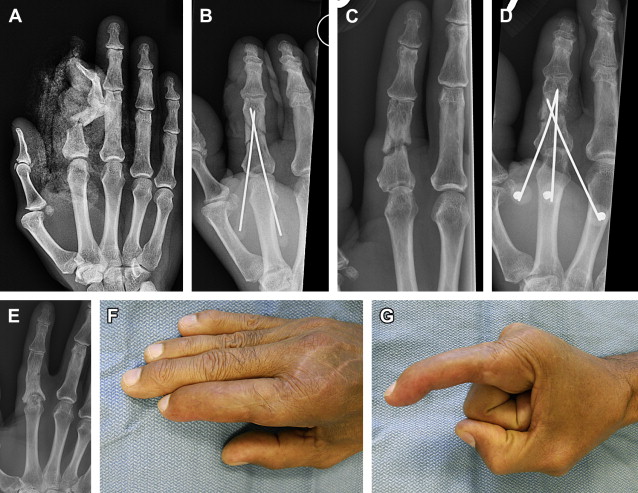

Malunions occur when a fracture heals in nonanatomic position; this can result in rotation, angulation, or shortening to varying degrees. Rotational deformities manifest with scissoring or crossing of the fingers in flexion ( Fig. 5 ). This appearance is often not evident with the fingers in extension, but can result in weakness and difficulty with dexterity. These rotational deformities typically occur following oblique or spiral fractures. Lateral angular deformities result from either intra-articular malunion with displacement of one condyle or with comminution and collapse on one side. These deformities are often evident with the digits in extension and are exacerbated with flexion, resulting in scissoring of the digit. When the fracture is inadequately treated, these deformities may result in a malunion.

For shaft nonunions, rigid fixation is preferred when there is adequate soft-tissue coverage. The plate size is typically larger than would be used for an acute fracture in the same location. Unfortunately, especially in the phalanges, the soft tissue is often compromised, making plate fixation impossible ( Fig. 3 ). The nonunion site is exposed and nonviable bone is debrided. The void is filled with bone graft and fixation is applied. Early motion is preferred to promote tendon gliding and to minimize adhesions, as these digits are typically stiff from the previous injury.

Amputation should be considered for cases with sensory loss, stiffness, persistent infection, or poor soft-tissue coverage. A stiff digit is often a liability to hand function and, even if the nonunion were to heal, the digit remains stiff and can impair hand function ( Fig. 4 ). Recovery following amputation is often rapid, and leads to improvement in function of the hand.